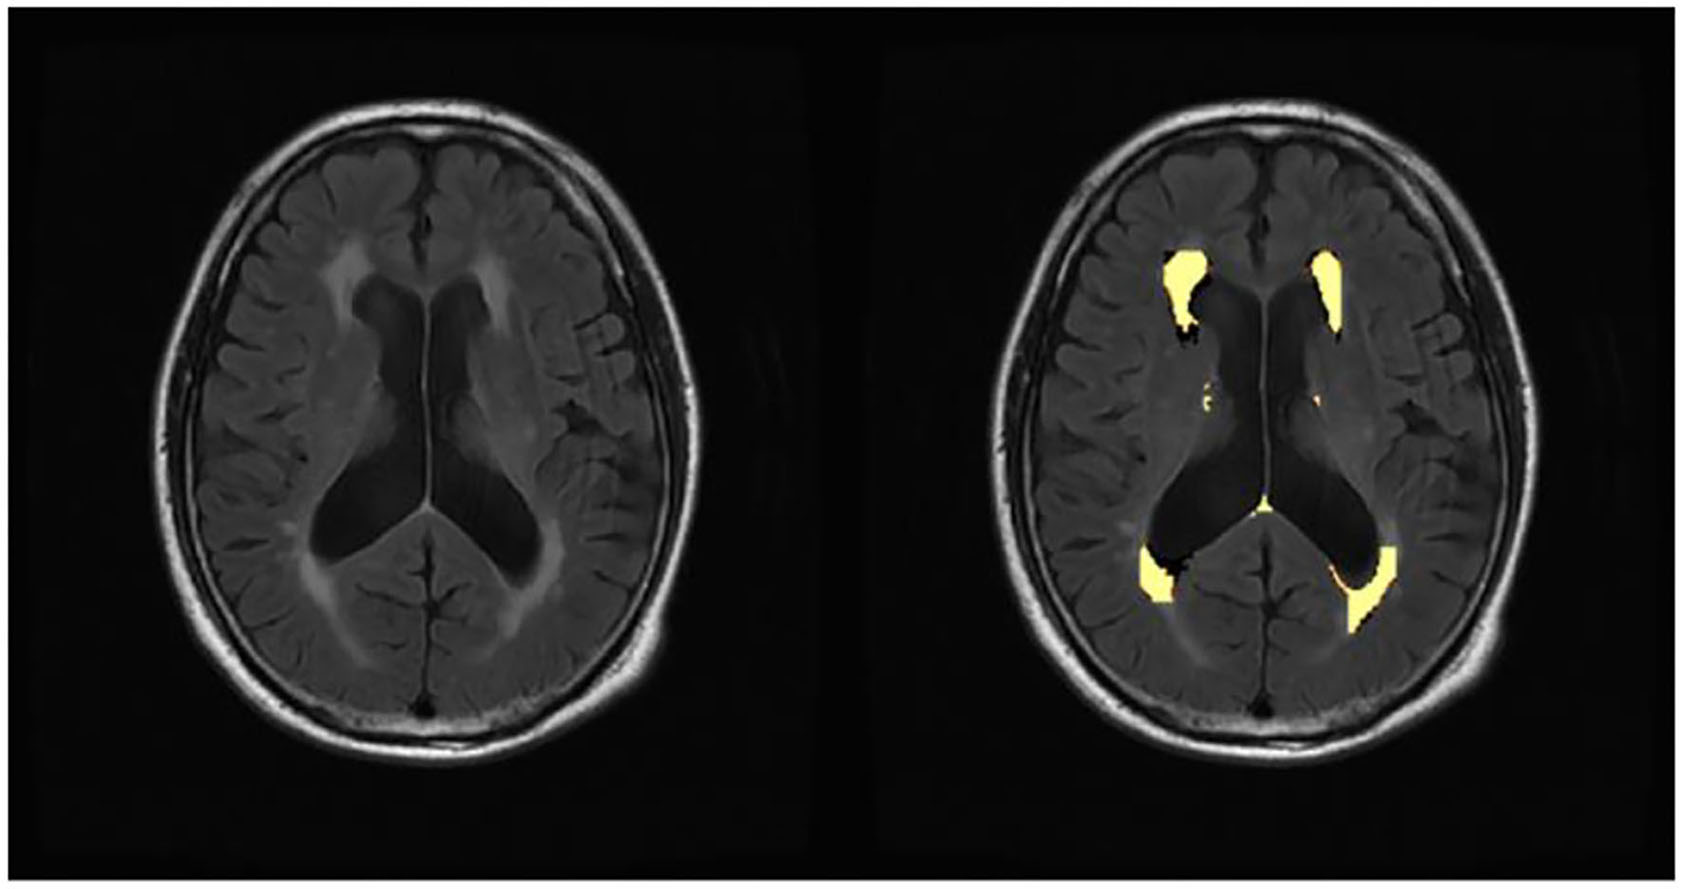

The WMH volume was segmented by the Lesion Growth Algorithm (LGA) from the LST toolbox (Lesion Segmentation Toolbox, version 3.0.0, Morphometry Group, Department of Neurology, Technische Universität München, Germany; www.statistical-modelling.de/lst.html) (41). This toolbox was established on SPM12 based on the probabilistic modeling and the region growing algorithm. The algorithm first segmented the T1-weighted images into GM/ WM/ CSF. Lesion belief maps were created by combining these data with the intensities on FLAIR. By thresholding these maps with a pre-chosen initial threshold (κ), initial binary lesion maps were obtained, which were subsequently grown along the voxels that appeared hyperintense on the FLAIR image. We finally obtained the lesion probability maps and the total WMH volume of bilateral cerebral hemispheres (Figure 1).

Figure 1

Automated white matter hyperintensity segmentations on sample subject fluid-attenuated inversion recovery scan by lesion growth algorithm.